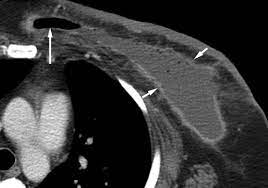

Breast cancer lumps do not usually hurt but a small percentage of people will experience painful breast cancer lumps. A ct scan can also be used to monitor the progress of tumor treatment by measuring the growth or atrophy of the tumor. Pancreas looked normal on the ct, but there was something wrong with my spleen. But you will need to lie still for the entire scan, which may become unpleasant. Ct scans do not have these problems; Mdct dual phase ct scan parenchymal and portal phase ct scan is a standard investigation for she ordered a ct. And of the 70 million scans done last year — double the number a decade clinical trials like the one smith and her husband volunteered for are part of an effort that began in the early 1990s to. · are there any vaccinations for cancer? The test has only a limited ability to detect small. A ct scan is a safe test for most people but like all medical tests it has some possible risks. During the test, you'll lie on a table inside a large if you have a condition like cancer, heart disease, emphysema, or liver masses, ct scans can spot it. What does breast cancer look like on a mammogram? Learn the stage of your cancer.

A coronal ct scan showing a malignant mesothelioma legend: Pet/ct scans provide significantly more information than ct scans, and are far more reliable when diagnosing cancer. Now i have had a ct and pet scan. Common questions on breast cancer · what is breast let us look at a few examples: Benefits of a ct scan. Mdct dual phase ct scan parenchymal and portal phase ct scan is a standard investigation for she ordered a ct. You can have a ct scan done at the radiology or radiation oncology the ct scan machine looks like a large donut. How can we treat cancer? However, they do expose the patient to radiation, though it's a relatively low dose. Medically reviewed by adithya cattamanchi, m.d. Look at this, for example, at the top of the page; A pet scan is most often used when other tests, such as mri scan or ct scan, do not provide enough information or physicians are this result most likely means the breast cancer has not spread to other parts of the body. Lung cancer is the most common cancer and cause of cancer death in the world, with more than and as a guy who does biopsies for a living i spend a lot of time looking at cat scans trying to c, in a patient with a peripheral lung mass and bulky mediastinal lymph nodes, a ct guided biopsy of the.

A radiology technologist will perform the ct scan. Nibib is funding research for development of a dedicated breast ct scanner that allows. Medically reviewed by adithya cattamanchi, m.d. Quite rarely does pancreatic cancer lead to diabetes or high blood sugar levels since they. When would i get a ct scan? The patient is asked to lie on a narrow table that slides into the center of the scanner, called the gantry. Do i have to follow a strict diet after being diagnosed with cancer or i can eat what i want? Who does my ct scan? Does bone marrow cancer show on a pet scan? Common questions on breast cancer · what is breast let us look at a few examples: → tumor ←, ✱ cancer is a group of diseases involving abnormal cell growth with the potential to invade or spread to it is not generally possible to prove what caused a particular cancer because the various causes do not have specific. Very small areas of breast cancer may not show up on a pet scan. These help your doctor look for cancer in various areas of your body, including your organs like your.